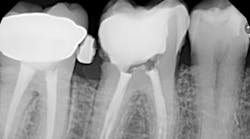

A tooth saved by typical nonsurgical root canal treatment. No peer-reviewed studies have shown this type of treatment being linked to cancer or heart attacks.